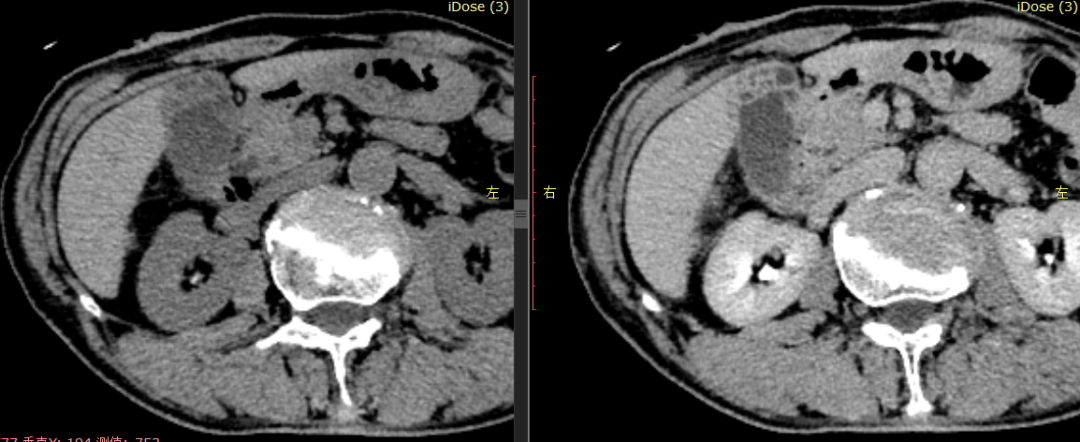

CASE 2